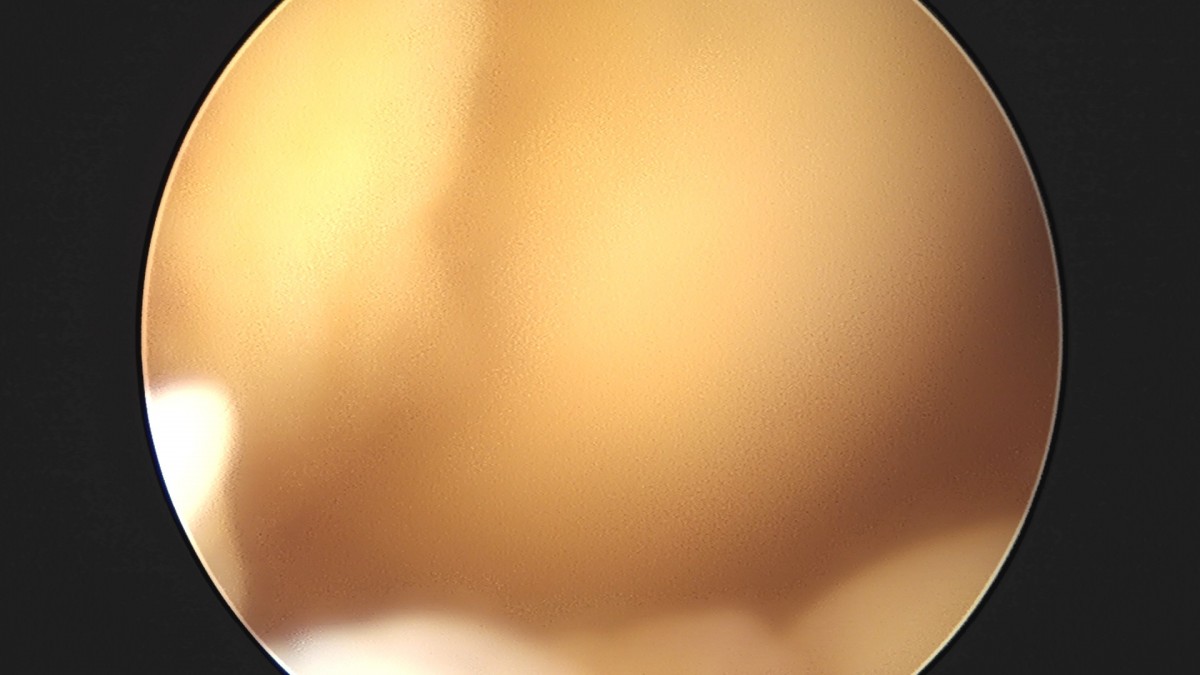

이재상원장님 무릎 전방십자인대 재건술 김태O 환자

dae765e4d9ac96aee867c9d6292d8784_1758007423_7423.jpg